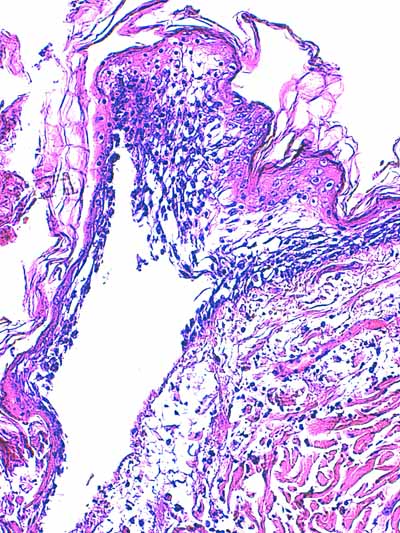

Photo 5 (Hémalun-Eosine X200) : l’épiderme, siège d’une dégénérescence réticulaire,

se détache et se désolidarise du derme superficiel, donnant naissance à une vésicule.

Légendes de la Photo 5 :

- Pointes de flèches turquoises : plancher de la vésicule sous-épidermique

- Ovale jaune : œdème et ballonnisation des acanthocytes épidermiques = zone de dégénérescence réticulaire de l’épiderme, qui fragilisé se détache du derme formant une vésicule sous-épidermique

- Double flèche orange : épaisseur épidermique

- Double flèche verte : épaisseur dermique

- Étoiles rouges : œdème dermique

- Flèches jaunes : fibres de collagène du derme

- Flèche turquoise : vésicule sous-épidermique

Photo 6 (Hémalun-Eosine X100) : on observe une nécrose de liquéfaction de l’épiderme.

Le derme est relativement silencieux, mais abrite des follicules pileux dont la

tige pilaire apparaît multi-fracturée, dont la gaine externe est fissurée ou dont

la membrane basale et la gaine fibreuse sont épaissie avec absence de gaine épithéliale externe.

Légendes de la Photo 6 :

- Pointes de flèches turquoises : couche cornée de l’épiderme (stratum corneum)

- Ovale jaune : follicules pileux anormaux

- Ronds marrons : nécrose de liquéfaction de l’épiderme

- Double flèche bleue : épaisseur hypodermique

- Étoiles rouges : tiges pilaires fracturées

- Flèche jaune : reliquats de gaine épithéliale externe du follicule pileux

- Étoile verte : membrane basale épaissie du follicule pileux

- Flèche turquoise : fissuration supra-basale au sein de la gaine épithéliale folliculaire externe